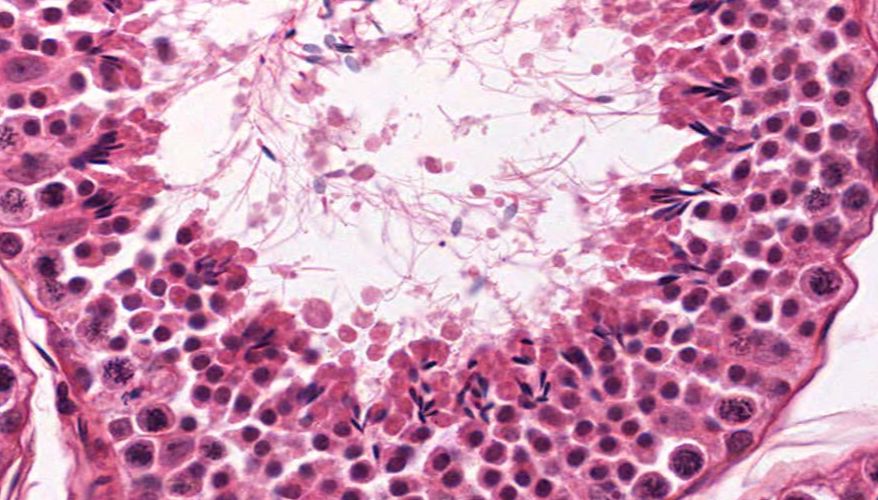

低倍镜:睾丸表面为鞘膜覆盖,其上皮为单层扁平上皮,鞘膜下是一层较厚的致密结缔组织,叫做白膜。白膜在睾丸后缘增厚,形成睾丸纵隔,其内可见不规则的腔隙,即睾丸网。睾丸内可见很多上皮性管道的切面,即生精小管的切面,呈圆形或椭圆形,管壁较厚,由生精上皮及其明显的基膜等组成。高倍镜:着重观察生精小管和其之间的睾丸间质。生精小管主要由生精上皮构成。生精上皮由生精细胞和支持细胞组成。生精细胞是一组细胞,依次自基膜向管腔面排列。

6.生精上皮

7.支持细胞

8.精原细胞

9.初级精母细胞

10.精子细胞

11.精子

12.睾丸间质细胞

15.精子发生